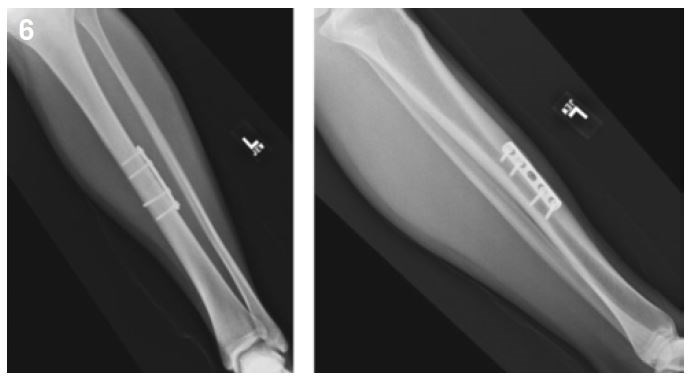

Considering the high rate of non-union, surgical management is widely recommended. It may be a simple compression plate on the convexity of the tibial at the level of the fracture site. For others, the placement of a centro-medullary nail will be necessary7,15,28 (Figures 6 and 7).

Figure 6: Mid shaft tibial stress fracture: osteosynthesis by plate.

Figure 7: Mid shaft tibial stress fracture: osteosynthesis by intramedullary nailling.